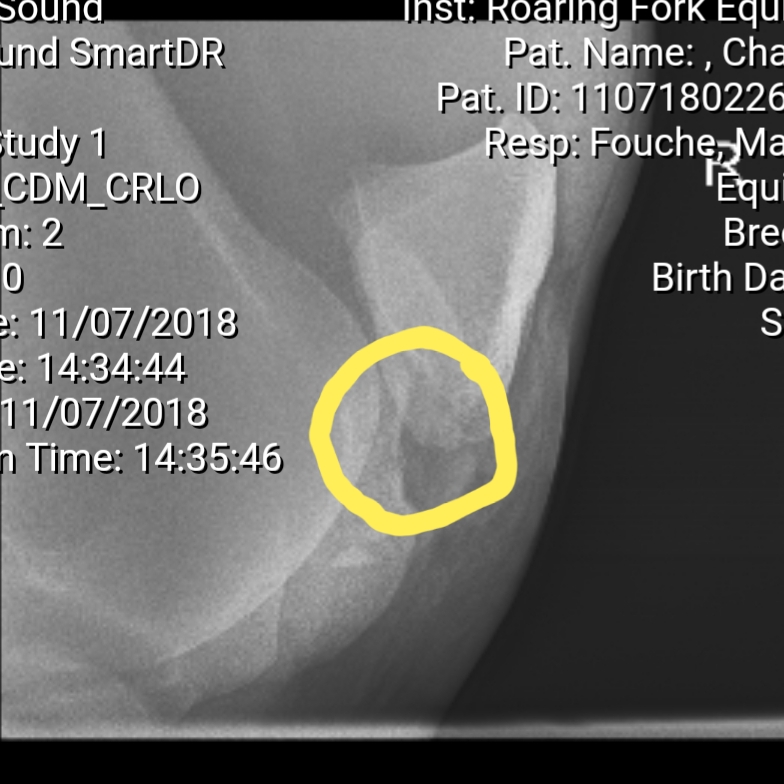

Chaco, if you know me or followed my blog for a while, went down in a race several years ago and was run over by two other horses. He got kicked in the stifle, broke his pelvis, and broke a rib. The kick in the stifle is what haunts him to this day. That kick caused three marbles the size of adult teeth to break off and meander and destroy the cartilage in his femoropatellar joint. I fine myself every time I call them chips because they are anything but chips. After three hours of arthroscopic surgery, it took that long due to difficulty finding one of the marbles, I’ve spent the past couple of years trying to maintain his stifle.

The three marbles before they were removed

You can see within the circle the area that broke off

Unfortunately, they never removed the bone chunks. (For the record, they were not chips. They were the size of your adult, front teeth.) Instead they blistered him probably so his muscles and tendons wouldn’t rub against the bone chunks. He raced for a year, and those chunks worked their damage on the femorotibial joint in his stifle. When I adopted him, we had them removed, but the damage was severe. I was told that he would never be truly sound, and each day was on borrowed time.

Chaco, as I mentioned in my last blog, went down in a race. He was brought up on the inside along the rail. All of his other races he went wide away from all of the traffic. He had a big stride. This time on the inside he clipped heels, went down, and two other horses went over him. One kicked his stifle breaking some of the bone off into big chunks. His pelvis was fractured along with a rib. He recovered and raced two months later winning his first race back.